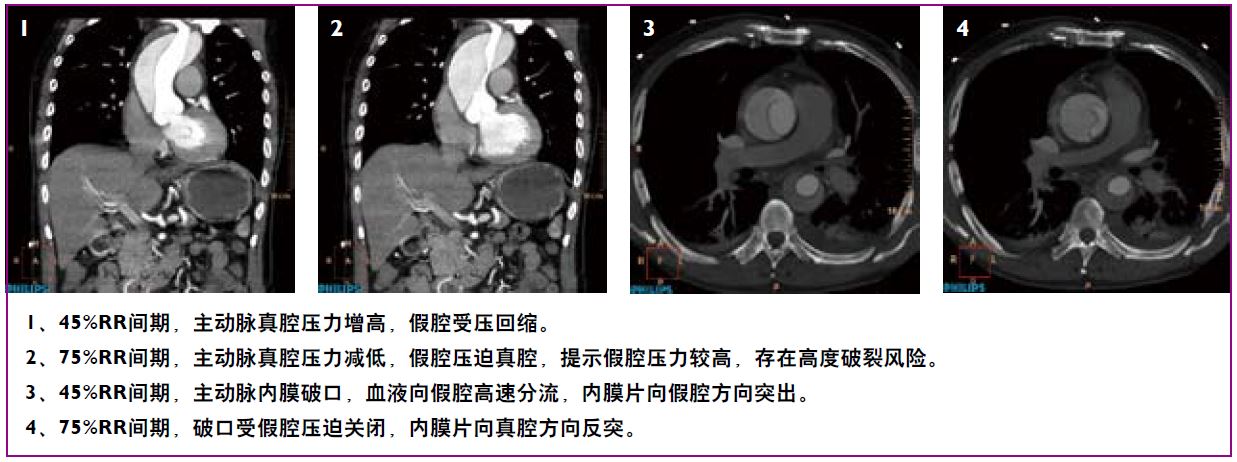

全景成像——基于宽体探测器及极速扫描实现无扫描范围限制、超低辐射剂量的高清动态全景成像,一次扫描,解剖细节及生理动态同时呈现。